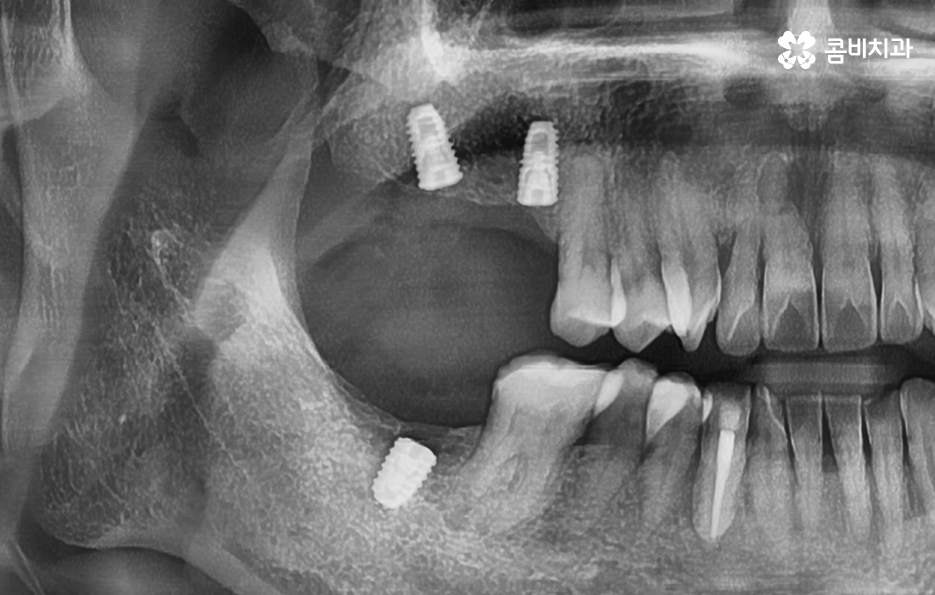

여기서는 일반적인 치료 과정이라는 점을 전제로 하고 있는데요. 잇몸 뼈 상태가 양호하고 건강한 상태인 경우에 임플란트를 위한 치과 내원 횟수와 기간이 약 45회, 34개월 정도로 예상되는 것이며 잇몸 뼈의 상태가 좋지 않아서 뼈이식이 필요하거나 잇몸 이식술이 필요한 경우에는 치과 내원 횟수와 치료 기간이 더 늘어날 수 있는데요

특히 노인분들의 경우에는 치아를 잃게 되는 주된 원인이 치주염이 심해져서 치아가 흔들리고 발치하게 되는 경우가 많으며 당뇨나 고혈압과 같은 전신질환이 있는 경우도 고려해야 하기 때문에 임플란트의 기본적인 치료 원리는 비슷하지만 각 개인에 따라서 치료기간과 치료 방법이 다소 차이가 날 수 있어요

일례로 요즘은 임플란트 하면 원데이임플란트가 빠른 치료 방법이 장점으로 부각되어 많이 알려져 있는데요. 원데이임플란트는 특히 앞니 치료에 적용하면 잇몸 라인의 보존과 임시치아를 빠르게 부착하여 심미적 부담감을 해소하고 치료 기간을 단축시킨다는 장점이 있지만 노인 분들의 경우 여러 치아를 잃은 상태에서 임플란트를 하는 경우가 많고 잇몸이 약하거나 전신건강이 좋지 않아서 회복력이 약하고 전신질환이 이미 있는 경우도 많기 때문에 오히려 안정성과 건강한 결과에 더 초점을 두실 필요가 있어요

따라서 어금니 임플란트 기간 단축만을 위해서 원데이임플란트를 적용하기 보다는 자신에게 적합한 치료 방법을 정밀검진을 통해 우선적으로 파악하는 것을 권하고 있어요